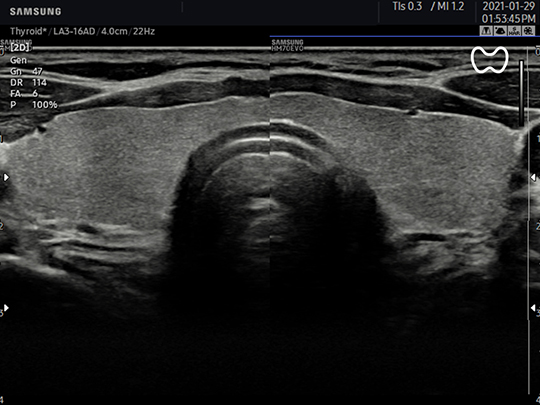

LA3-16AD

- Application: small parts, vascular, musculoskeletal, abdomen, obstetrics, gynecology, pediatric